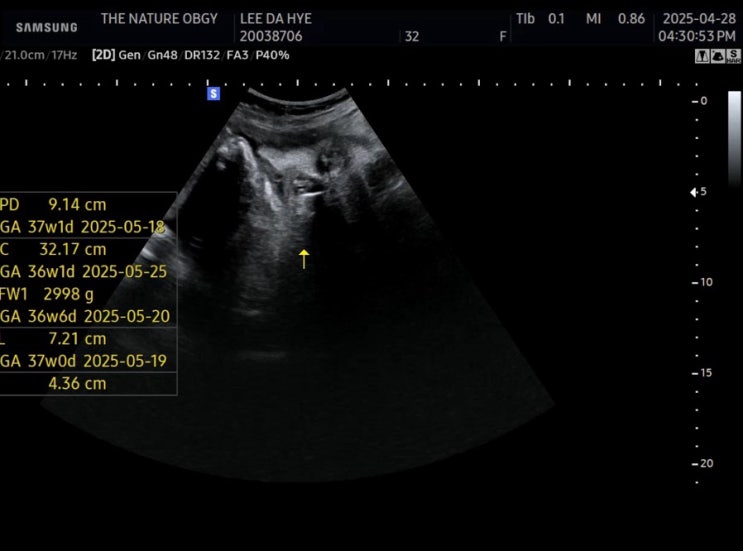

임신 36주차 - 마지막 정기검진 , 수술 전 왁싱 등등